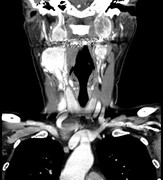

What happens in vagus: a case of recurrent paraganglioma with malignant transformation and an updated treatment algorithm

Natalie M. Ertz-Archambault and others

Journal of Surgical Case Reports, Volume 2016, Issue 2, February 2016, rjw012, https://doi.org/10.1093/jscr/rjw012